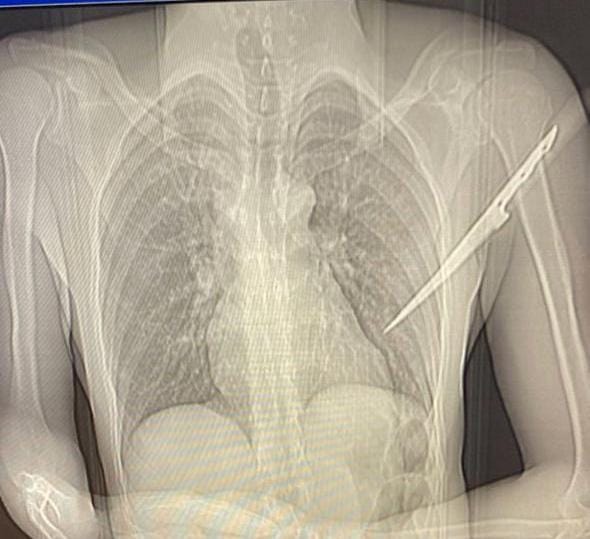

As informações do estado de saúde deste homem é que ele não corre o risco de morrer. O mesmo ficou em atendimento médico e necessitou passar por cirurgia para remoção da faca que ficou cravada nas costas.